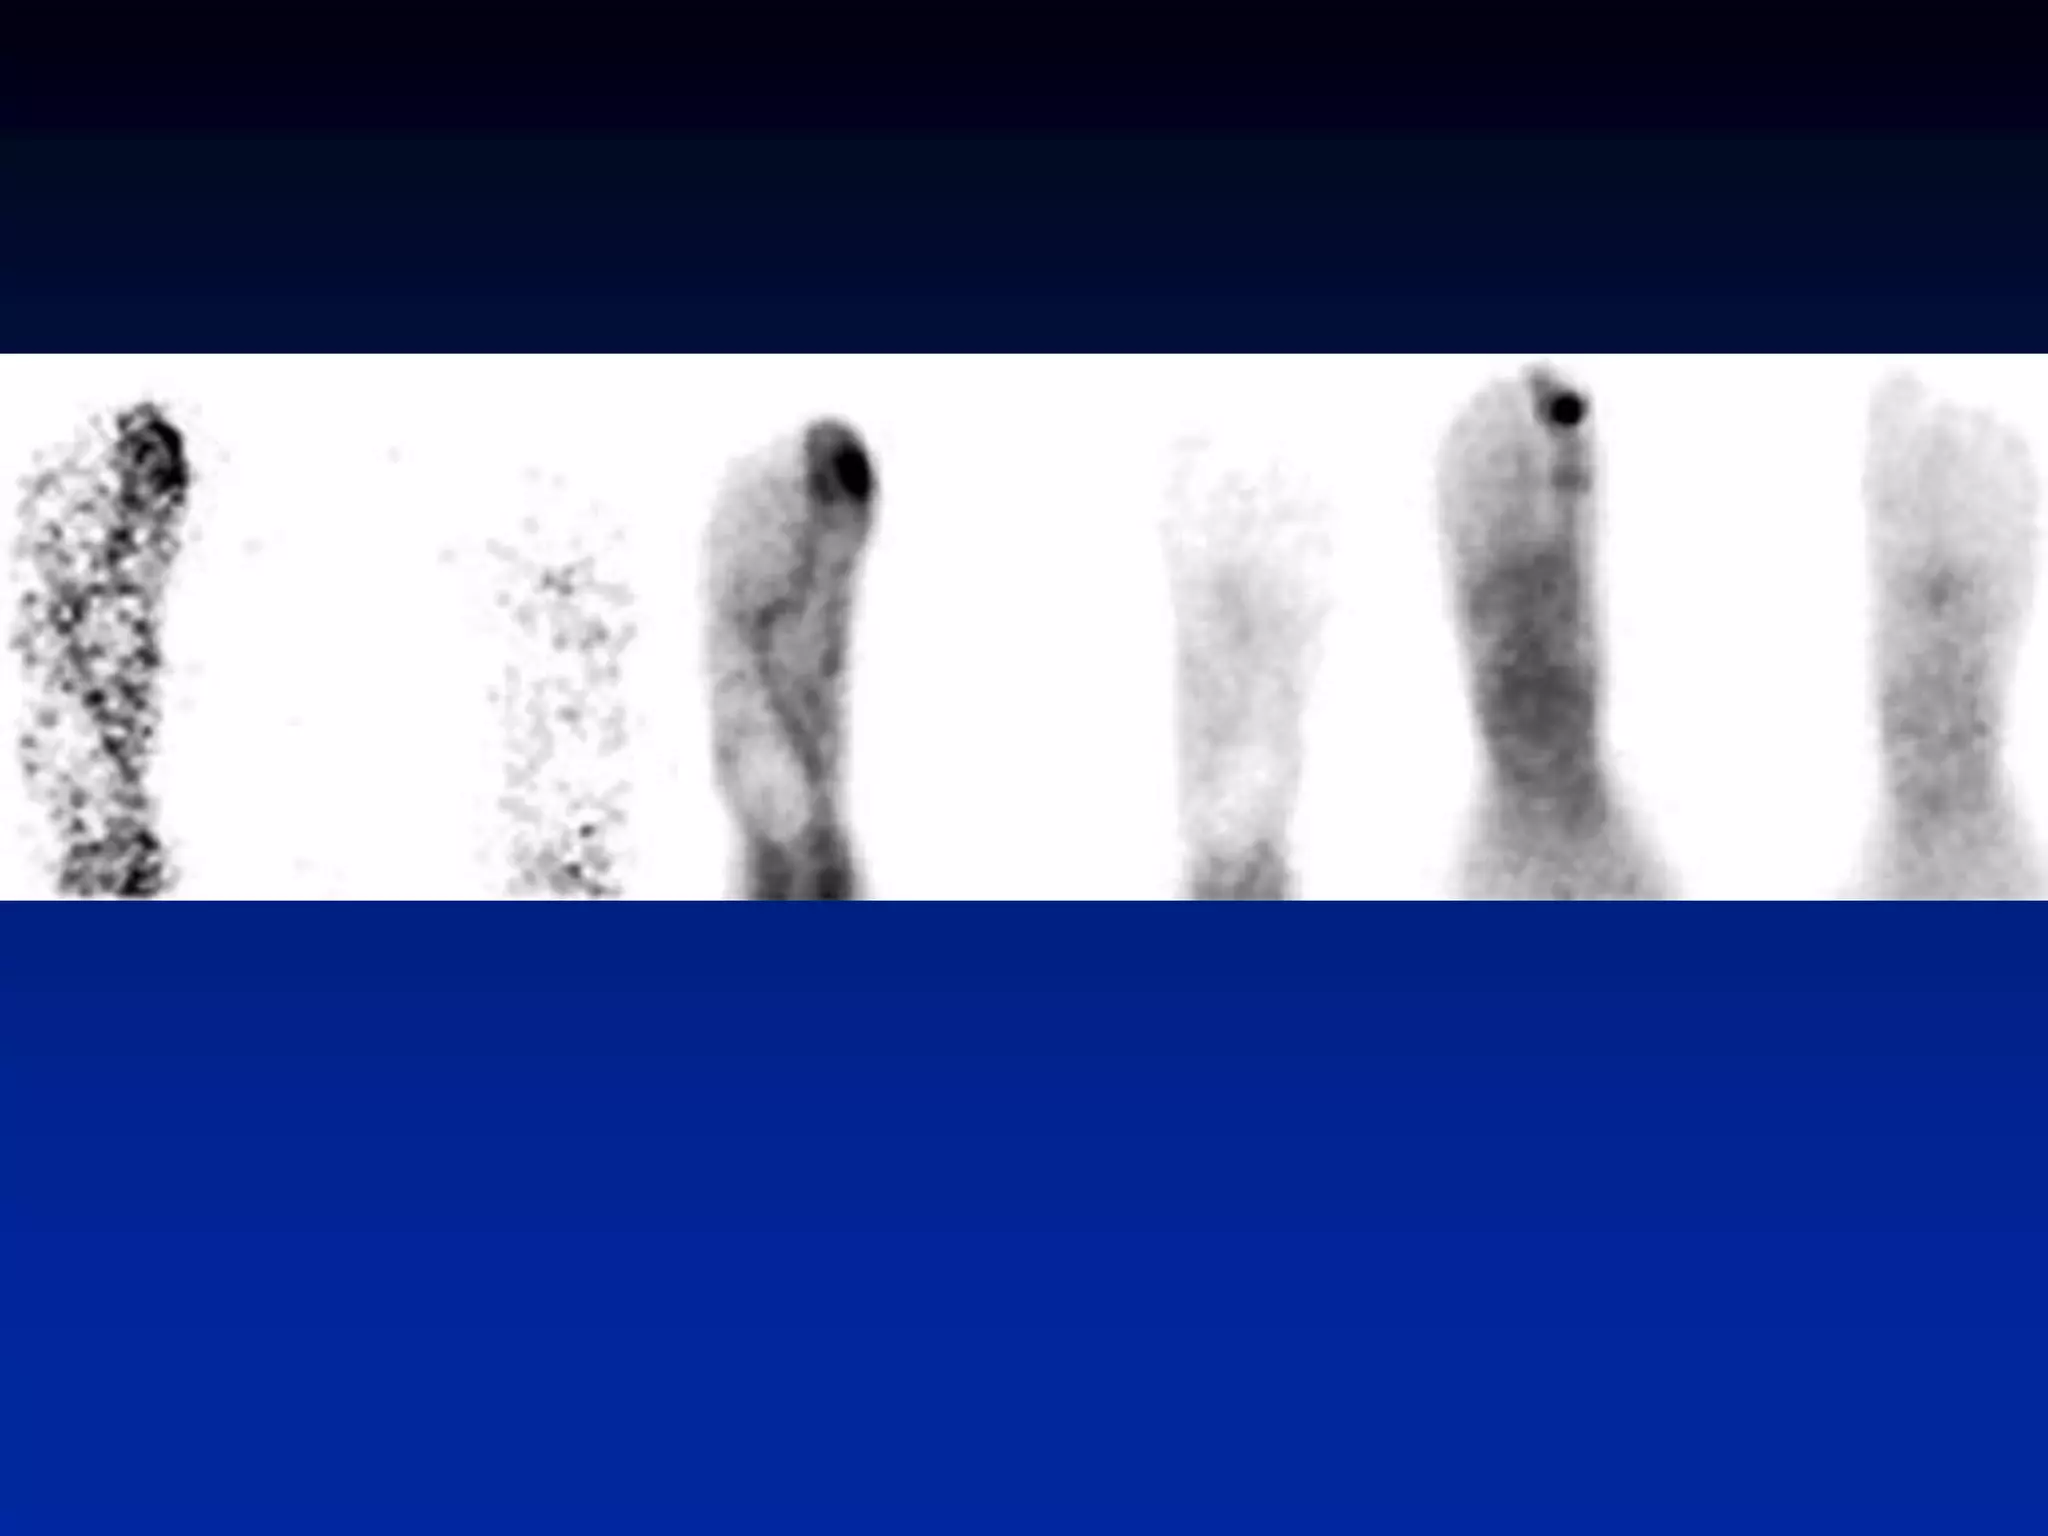

Legg-Calve-Perthes • early imagingphoton deficient lesion • increased activity with healing (for months)

• 58.